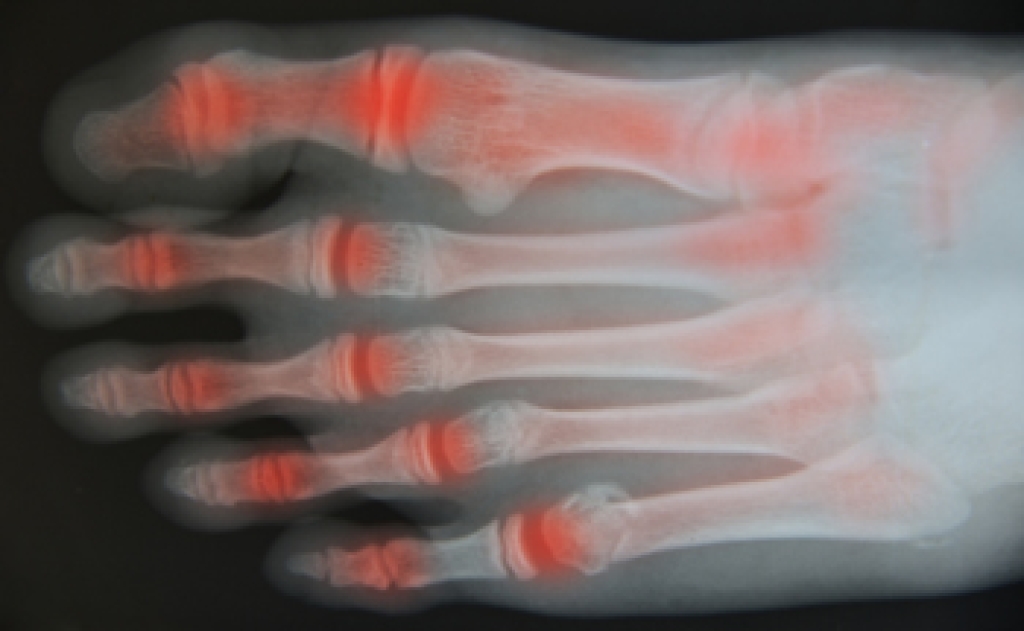

In many cases the cause of toe pain is obvious, but in others, a podiatrist may want to use more advanced methods to determine the problem. These can range from simple visual inspections and sensation tests to X-rays and MRI scans. Prior medical history, family medical history, and any recent physical traumatic events will all be taken into consideration for a proper diagnosis.